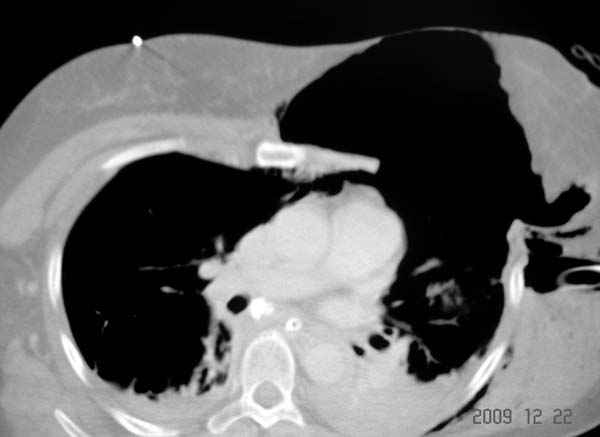

К нам поступила больная 56 лет после автоаварии в бессознательном состоянии, которая срочно заинтубирована в приемном отделении и сделаны необходимые исследования. Данные КТ и рентген показали перелом дистального бедра и Dissociation upper extremity - закрытый отрыв левой верхней конечности на уровне грудинно-ключичного сочленения и множественные переломы ребер.

На поверхности грудной клетки из-за полного разрыва грудной мышцы под кожей заметно биение сердца и след от ремня безопасности. Грудная клетка расширена из-за смещения верхней конечности вверх и латерально. Признаков васкулярного повреждения нет, и из-за отсутствия сознания не смогли определить наличия повреждения нервов.

После кожного разреза обнаружили полный разрыв грудной мышцы и повреждение перикард от уровня второго до восьмого ребер. Хирург находился с нами и после нашей работы зафиксировал повреждение перикарда и разрыв грудной мышцы.